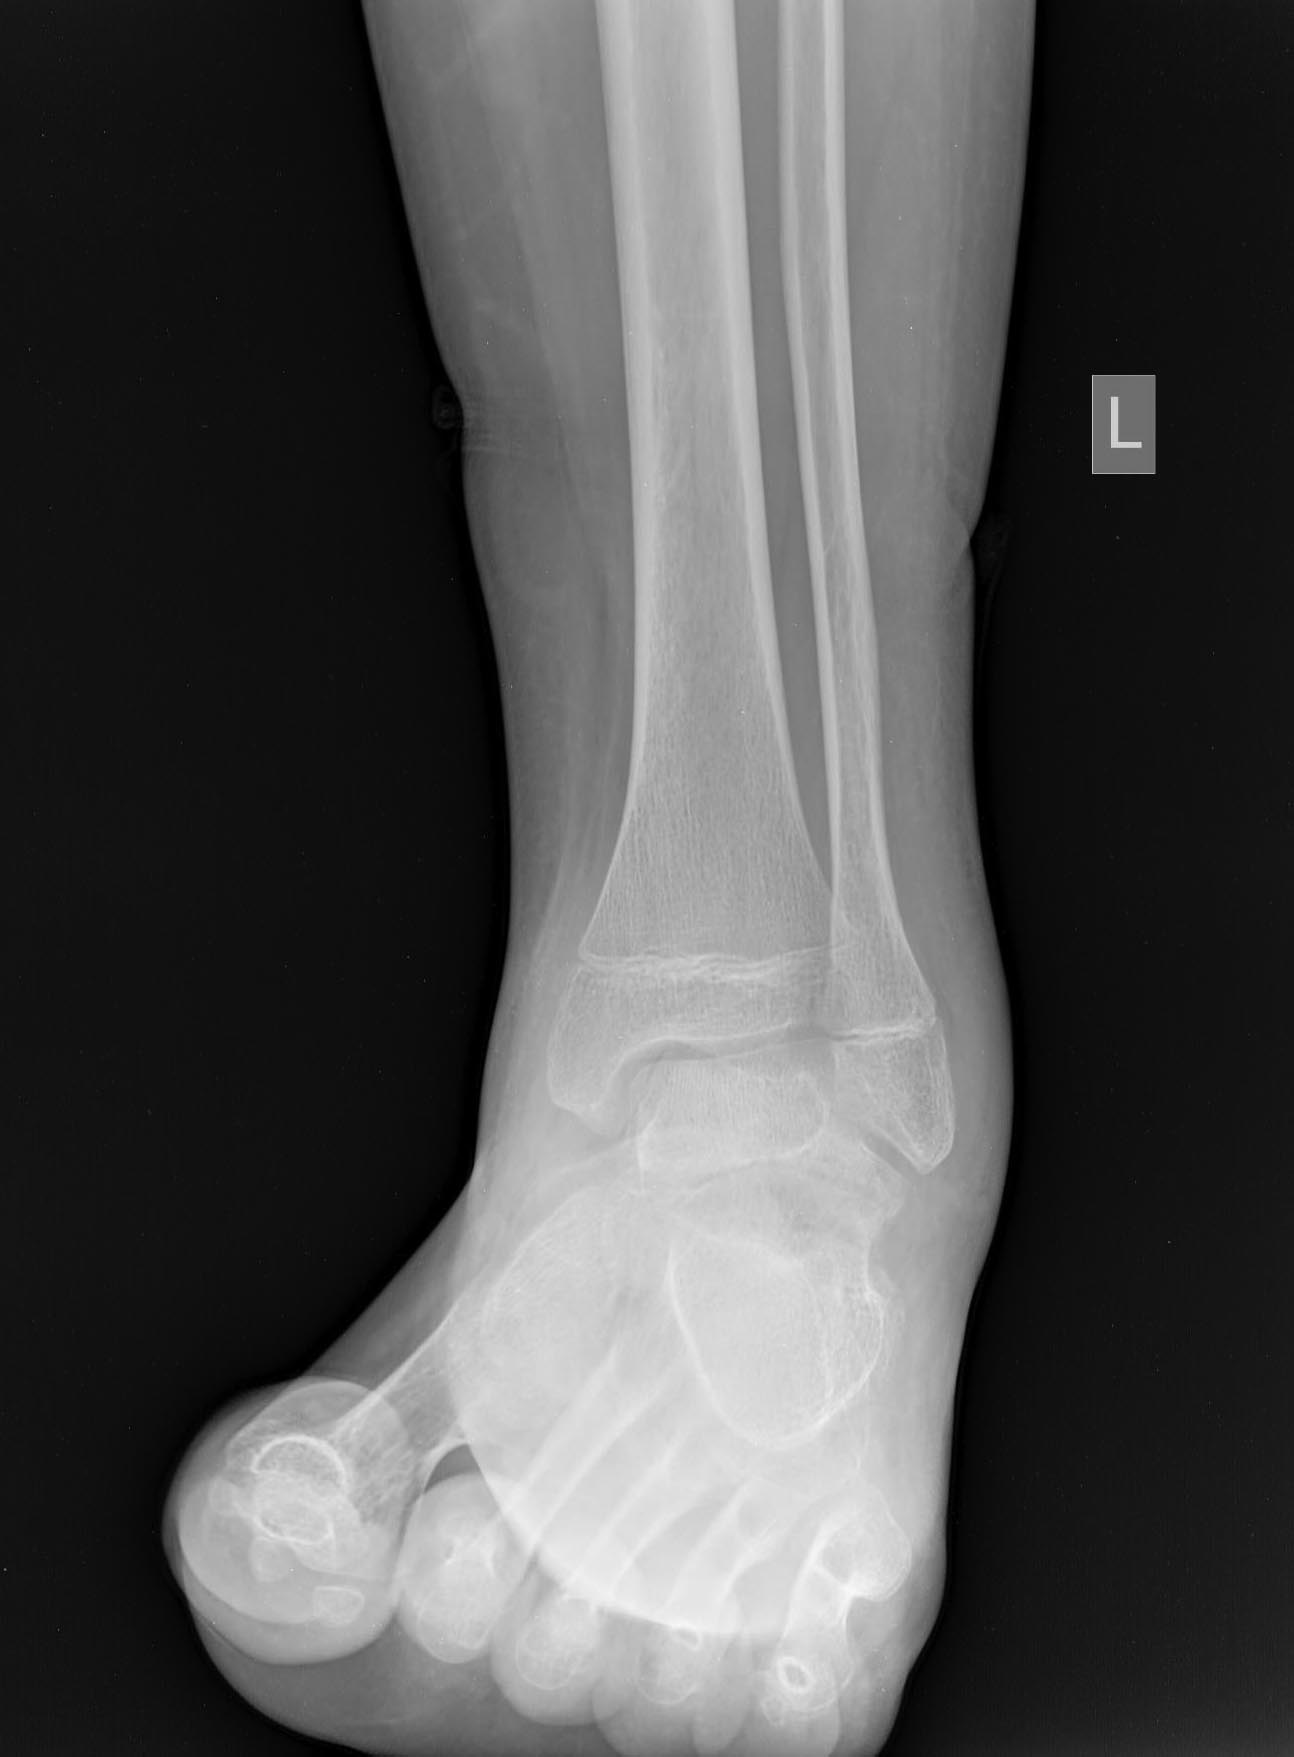

Вчера был на консультации. Травма 2 мес. назад. На снимках перелом шейки

таранной кости в детской больнице не увидели.

Сказали, мол, растяжение - наступай. Ну вот он и наступает. Сейчас ходит

с тростью.

Что делать? Подтаранный артродез с gjgsnrjq сохранить голеностопный

сустав, или большеберцово-пяточный блок с использованием остатка

таранной кости в качестве трансплантата?

A boy 14 was referred yesterday.

Injured 2 mnth ago, the fracture was missed somewhere, and he was

recommended to walk. And he was trying to do this all that time. Now he

is able to walk with cane.

Either subtalar fusion with attempt of ankle preservation, or

tibio-calcaneal fusion with the use of remnant of the talar dome as a graft?

How would you manage this case?